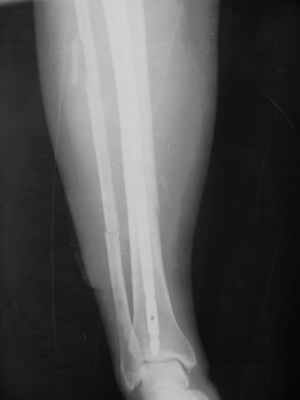

Здравствуйте уважаемые коллеги. Позвольте поделиться опытом применения интрамедуллярного остеосинтеза большеберцовой кости имплантатами компании ?Остеомед" с запатентованной прицельно-навигационной системой для дистального блокирования ?Интерлок". Для определения длинны и диаметра стержня использовали линейку-шаблон, позволяющей с легкостью рассчитать длину и диаметр стержня с проекцинно искаженными размерами, как конечности, так и линейки-шаблона.Дистракцию производили с помощью спицевого дистрактора с последующей закрытой репозицией отломков винтами Шанца. Все основные этапы производили по методике АО, гарантированное дистальное блокирование достигается за счет центрирования отверстий, путем контролирования смещения стержня в костномозговом канале в сагиттальной плоскости. Клинический пример:Больная Я. 45 лет, пострадала в результате случайного падения на улице 19.12.2005., имеет место открытый 1 степени перелом обеих костей левой голени со смещением отломков.произведена закрытая репозиция перелома с последующим введением стержня (на данном этапе производился рентген-контроль)Убедившись в достаточной репозиции перелома, произведено дистальное и проксимальное блокирование интрамедуллярного стержня.Общее время затраченное на оперативное вмешательство составило 45 минут.

Ну и наверно уже результаты есть, с декабря прошлого года-то?